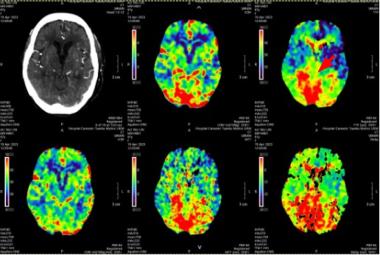

Defying All Odds: Successful Thrombolysis in a Nonagenarian with Posterior Circulation Infarct